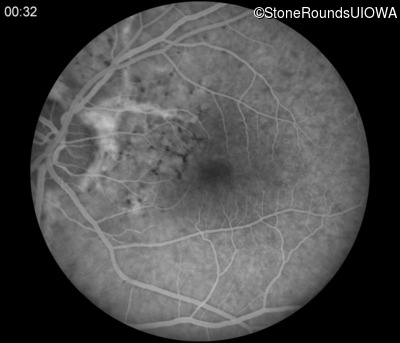

Fluorescein Angiography - Right - 20/20 -1

Exemplar